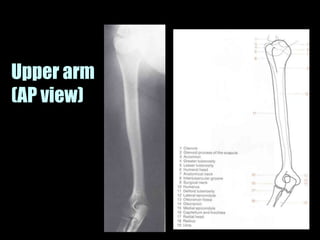

This document provides an overview of normal musculoskeletal imaging. It discusses basic x-ray concepts and densities. It then reviews normal anatomy as seen on x-rays of the skull, spine, pelvis, chest, and extremities. Key anatomical structures are labeled on example x-rays for the shoulder, hip, knee, and foot. Quizzes are included to test recognition of anatomical structures and patient age based on x-rays.